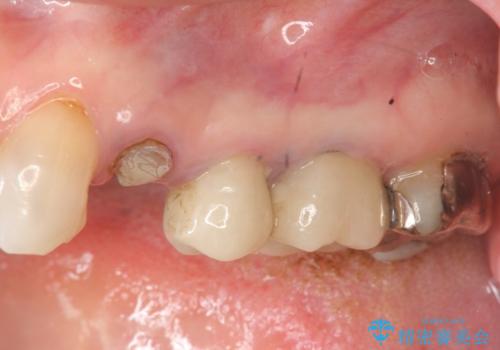

- グラグラする小臼歯の治療、全体的な治療のやりかえを希望され来院されました。

歯の穿孔(内部穴が開いている状態)破折等、歯を保存することができない問題が小臼歯には認められたので抜去を行います。